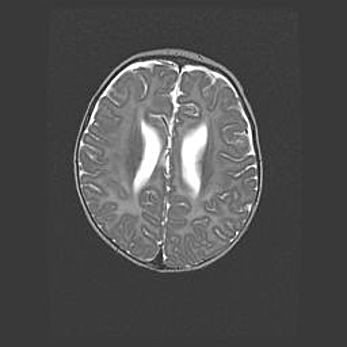

Множественные кисты обоих полушарий головного мозга, наибольшая из них в правой затылочной области. Ассиметричная атрофическая гидроцефалия.

Возраст: 7 месяцев

Вес: 5660 г

Пол: мужской

Окружность головы: 41,5 см

Срок гестации: 28-29 недель

Кисты головного мозга развиваются в результате многоочаговых некрозов вещества мозга и возникают вследствие перенесенной перинатальной инфекции, менингитов, энцефалитов, асфиксии, родовой травмы, расстройств мозгового кровообращения различного генеза. Образованию кист в веществе головного мозга плодов и новорожденных способствуют такие факторы, как высокое содержание в нем воды, недостаточная (или отсутствие) миелинизация и слабая астроглиальная реакция на повреждение.

Кисты могут сочетаться с гидроцефалией и другими поражениями головного мозга.